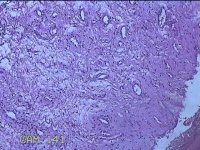

性别

女

年龄

54岁

临床诊断

宫颈上皮内瘤变Ⅰ级

一般病史

反复阴道脱出肿物3年余。

标本名称

宫颈组织

大体所见

灰白暗红色组织4.8x1.5x0.3cm一块,肥大,糜烂,切面灰白粉红色,质软

图1